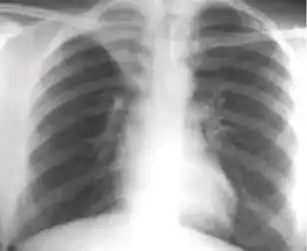

Radiology (X-rays) is used in the diagnosis of tuberculosis. Abnormalities on chest radiographs may be suggestive of, but are never diagnostic of TB, but can be used to rule out pulmonary TB.

In active pulmonary TB, infiltrates or consolidations and/or cavities are often seen in the upper lungs with or without mediastinal or hilar lymphadenopathy.[1] However, lesions may appear anywhere in the lungs. In HIV and other immunosuppressed persons, any abnormality may indicate TB or the chest X-ray may even appear entirely normal.[1]

Abnormalities on chest radiographs may be suggestive of, but are never diagnostic of, TB.[1] However, if a person has a positive response to the tuberculin skin test and no symptoms of the disease, chest radiographs can be used to rule out the possibility of pulmonary TB.